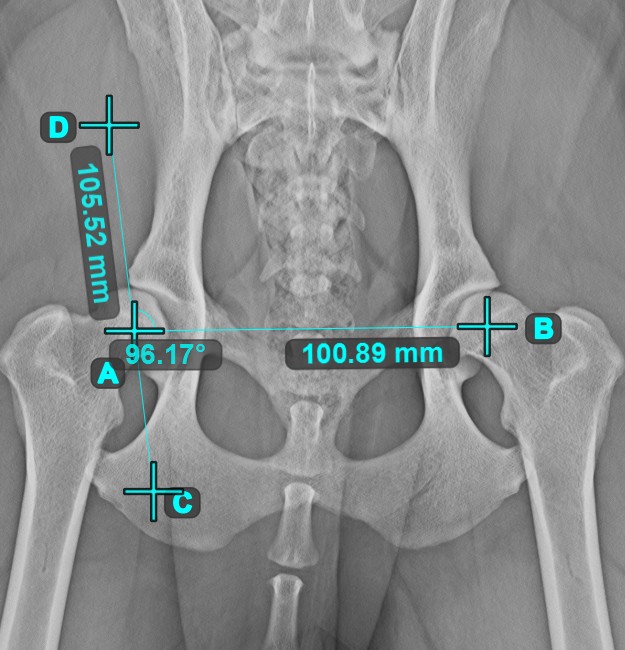

Angle of Lines¶

Select the tool from the left toolbar and assign it to one of the available mouse buttons. Start by selecting the first line from the ones already drawn on the scene, or place the start and end points to create the line. Follow the same steps for the second line of the measurement. The angle between the two lines will be automatically calculated.

Modify the start and end points of both lines by using the Select/Move Item tool. The angle between the two lines will be automatically recalculated.

Information

If two lines do not intersect directly, the angle of their extended projections on the scene will be calculated.